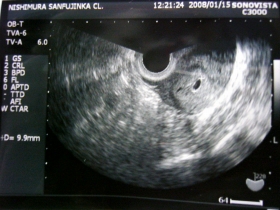

こんな点が。1ヵ月後にはこんな↓ヒト型。 画面に映し出されるまで。心臓が痛いぐらいドキドキします。私だけ?内診の診察室に入って、名前確認されて、カーテンのドア側で下だけ全部脱いで。アノ椅子に座って、ものすごいカッコで。おなかの上でカーテンで自分側と先生側を区切られてて。何されてるか全然分からない状況で。自分側にあるディスプレイに、自分のお腹の中が映し出されるのを待つんですが。最初は、子宮に着床しているか。でドキドキ。次は、大きくなっているか。でドキドキ。次は、心拍が確認できるか。でドキドキ。次は、ヒト型になっているか。でドキドキ。これからも、指がみえるかとか性別がわかるかとか。毎回めちゃくちゃドキドキしそうです。りりぃままからりりぃがお腹にいるとき、次の超音波の時消えてそうで怖い。ってメールが来て。実感もなく大丈夫だよって言ってたけど。今、まさに、その気持ちそのまま。消えてたら・・心拍なかったら・・大きくなってなかったら・・。そういうの考えちゃう。でも、逆に、大きくなってるはずって信じてる自分がいて。ディスプレイに映ると心底ε-(´∀`*)ホッとする。今はなんだか産む時の痛みとか産んだ後大変さとか、そういうのを心配する余裕はないです。タマタマなのかもしれませんが。内診は男性の先生より女性の先生の方が丁寧な気がしますYO。

私の中に。もう一つ別の命が宿りました。いろいろな喜びと。いろいろな不安と。いろいろな希望と。いろいろな戸惑い。たくさんの想いと一緒に私のところに来てくれました。5週目のとき、小さすぎると言われて。その日から1週間。閣下と二人、祈るような毎日でした。それでも、名前を考えたり、話しかけたり。閣下と二人、少しずつ親になる準備を始めました。6週目で、心拍を確認したときは。本当に本当に安心しました。10週目の検診で、ヒト型になった命を見ました。頭があって、腕があって足があって。そのコトが奇跡なんだと実感しました。今日は先週行けなかった13週の検診でした。お腹の上から私の心音とは別の心音を聴きました。ものすごく順調だと言われても日々不安だらけです。妊娠ってもっと幸せで幸せで。毎日をハッピーに過ごせるのかと思っていました。病院に行かないといるかどうかも確認できない小さな命への責任と不安で。産まれるまでも精神的にはすごく大変です。まだ安定期になっていないので、報告にはちょっと早いですが。でも。誘ってくれた飲み会に参加できなかったり。大切な人の送別会に行けなかったり。招待してもらえたら嬉しいなと思っていた披露宴に行けなかったり。周期的に有休をとったり。私の生活にも多少の変化が出てきて。そうなのかなーと思う人もいると思うので。まだ、おめでとうには早いけど。私の中にもう一人育ちつつあることをココでお知らせします。授かれるかどうかも分からなかったこの命を。私のとこに来てくれなくてもしょうがないと思っていたこの命を。それでも願ってやまなかったこの命を。大事に大事に育んでいきたいと思います。とりあえず安定期になるまで大人しくします。安定期になったら、産んでからはできないことをしまくりたいです(σ・∀・)σYO!!